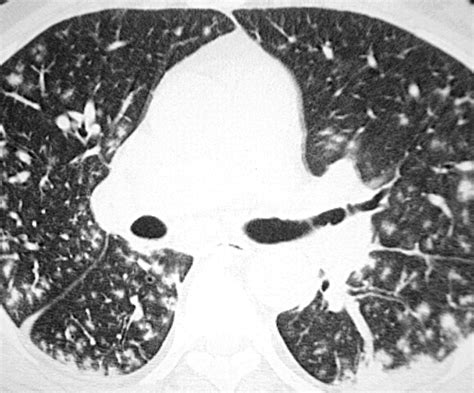

The tree in bud opacities appearance is fundamentally a reflection of airway pathology. On a CT scan, the "tree" component represents dilated, fluid-filled bronchioles (the smallest airways in the lung), while the "buds" represent the accumulation of mucus, pus, or fluid in the acini, which are the functional units of the lung located at the ends of these bronchioles. This pattern typically suggests that something is causing inflammation, infection, or obstruction within the small airways.

Because these opacities are located in the periphery of the lungs, they are easily distinguished from larger airway diseases. Radiologists look for these clusters of small nodules that connect to a branching structure. When you see this term on your report, it indicates that the air spaces are being filled with abnormal material, effectively "plugging" them and creating the characteristic visual pattern.